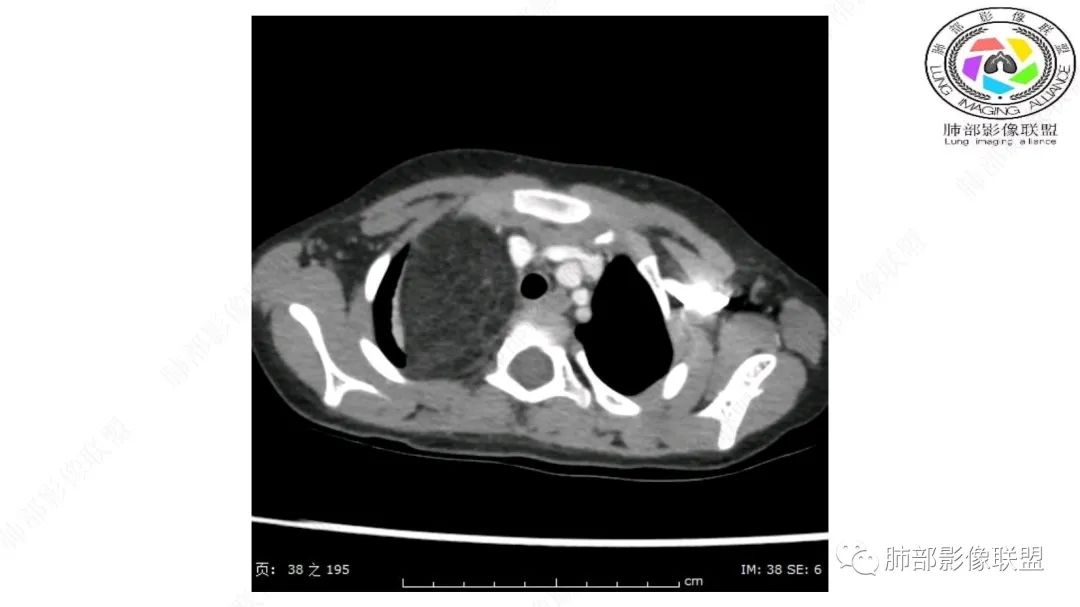

右上纵隔混杂密度肿块,边缘光整,与纵隔分界清,其内多发脂肪密度,增强无明显强化,其内血管穿行,考虑纵隔脂肪母细胞瘤,鉴别畸胎瘤,脂肪肉瘤。

右纵隔团状,密度不均,脂肪密度为主,内可见腺体样组织,类似乳腺,病灶边缘有分叶,与胸腺关系密切,增强后血管穿行。考虑胸腺脂肪瘤(不典型垂乳征),鉴别畸胎瘤。

三岁小儿,右侧纵隔巨大脂肪密度肿块,肺动脉穿行其中,密度欠均匀,未见明确实性成分,纵隔脂肪母细胞瘤,冬眠瘤鉴别纵隔脂肪增多症(多弥漫对称)。

病灶属于交界区,主体位于肺内,占位效应明显,前方突入胸壁,胸腺受压变形,胸膜显示欠清楚;病灶包绕上叶肺动脉;似乎有体动脉供血。符合肺内的点:包绕上叶肺动脉分支;符合纵隔的点:前方似乎突入胸壁,与胸腺关系比较密切,但是与上腔静脉的关系提示病灶不支持纵隔来源,前纵隔的常规会将上腔静脉受压后移、外移,这是不符合的。

2.肺动脉穿行也许是肺内来源最重要支持点!